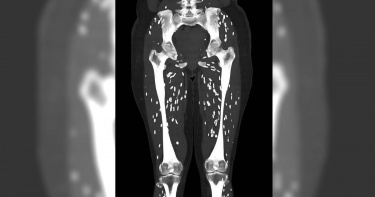

超級細菌太可怕!年輕女子感染後「肺部全是洞」 2周內不幸逝世

澳洲東南部新南威爾斯州一名29歲的年輕女子艾許莉(Ashley Timbery),原先身體狀況十分健康,但在意外感染了「超級細菌」後,短短2周時間,她就因為肺炎、敗血症等症狀而離世。根據英國《鏡報》(The Mirror)的報導,艾許莉於2月15日在家中突然倒地不起,並由其兄弟送她至醫院急救。經過醫院診斷,醫生發現艾許莉已經感染了「超級細菌MRSA」(全稱抗甲氧苯青黴素金黃色葡萄球菌)。艾許莉的表弟指出,她在突然暈倒前幾天,只有感到輕微不適、昏昏欲睡而已,身上亦長了幾處癤子,後來「超級細菌MRSA」攻擊了艾許莉的所有器官,並使她罹患了肺炎、肺部塌陷、敗血症等,最後帶走艾許莉的性命。艾許莉的表弟進一步表示,「當她到達醫院時,她實際上已經死了」,當時醫師趕緊為艾許莉施行心臟復甦和保溫,而據CT掃描結果顯示,艾許莉的肺部因肺炎而堵塞,蟲子棲息在她的肺腔裡,讓她的肺部充滿了許多坑洞。對於這個病症,英國國民保健署(NHS)解釋,「超級細菌MRSA」通常寄生在人類的皮膚與鼻腔中,如果通過傷口而造成皮膚感染,可能出現如紅腫、化膿、蜂窩性組織炎等症狀,萬一進入到體內,便可能導致嚴重感染,使人開始高燒、呼吸困難、發冷、意識混亂等等,需要立即使用抗生素進行治療,若救治不及時,便可能引起敗血症。